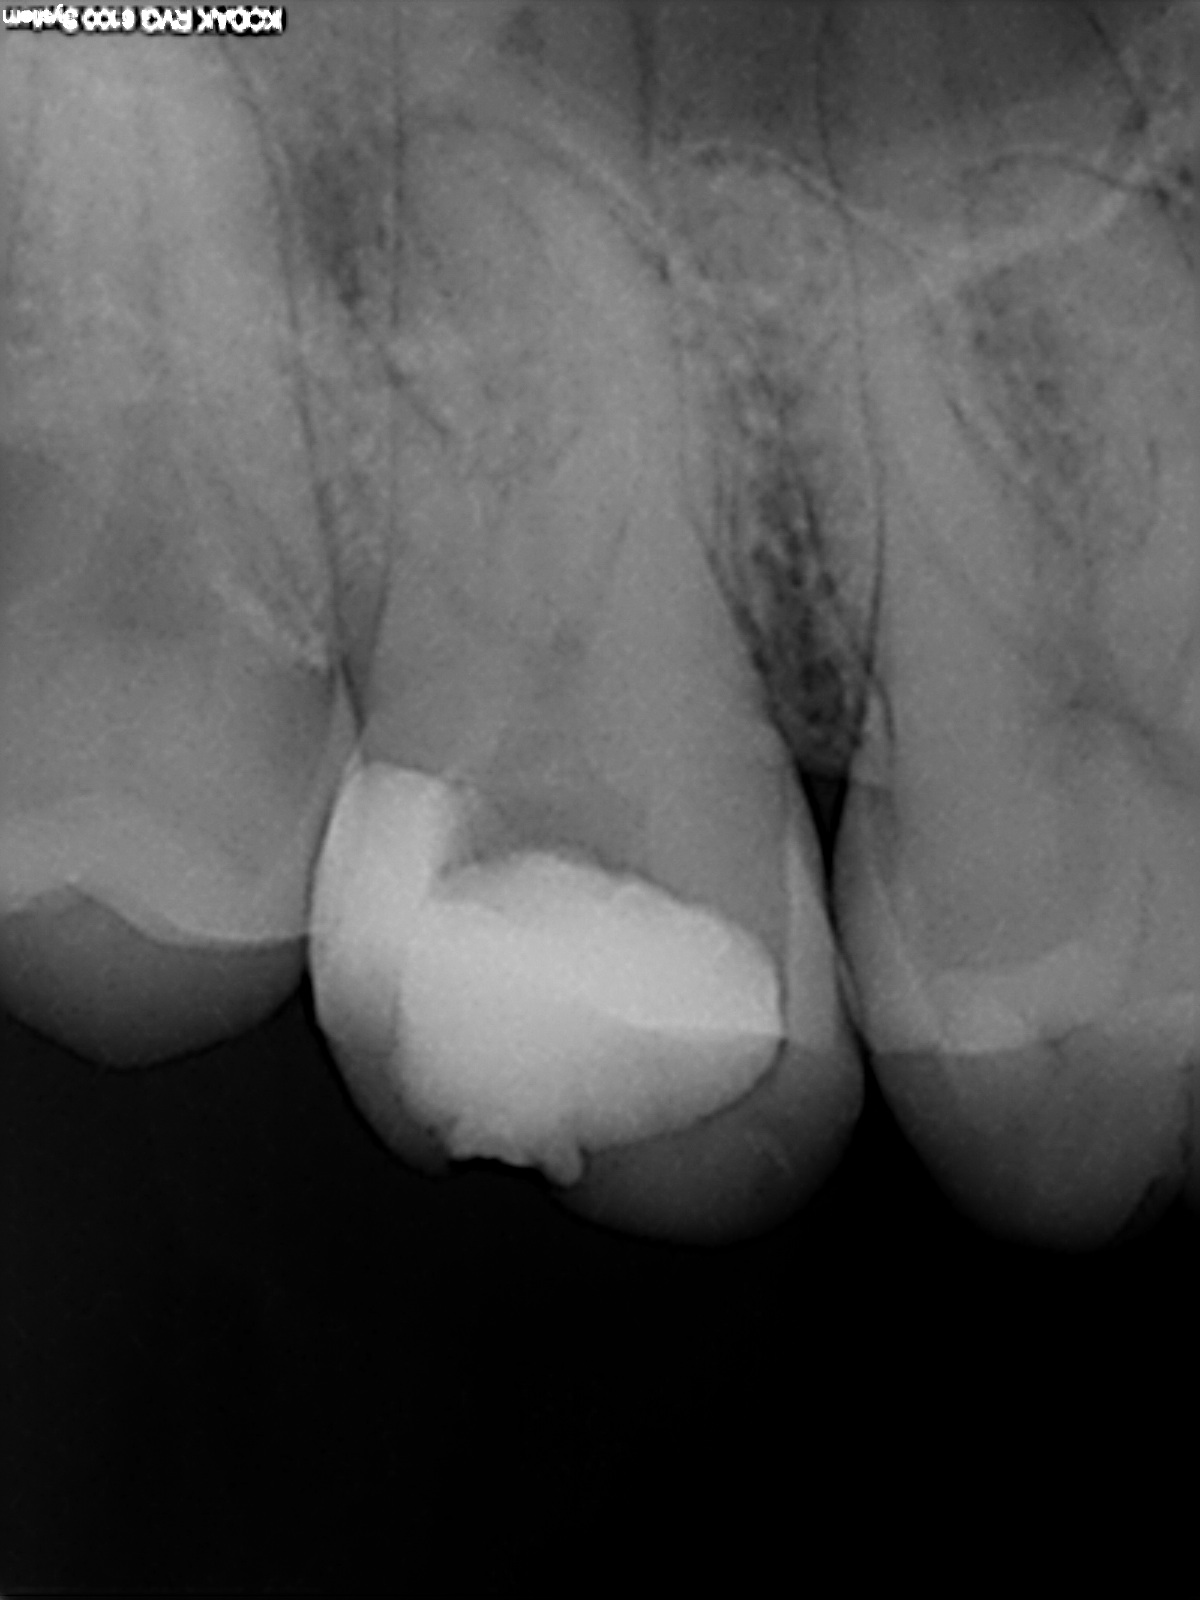

R1 Veröffentlicht 20. Januar 2014 am 1200 × 1600 in Was würden Sie machen, wenn es Ihr Zahn wäre? Ausgangsbild